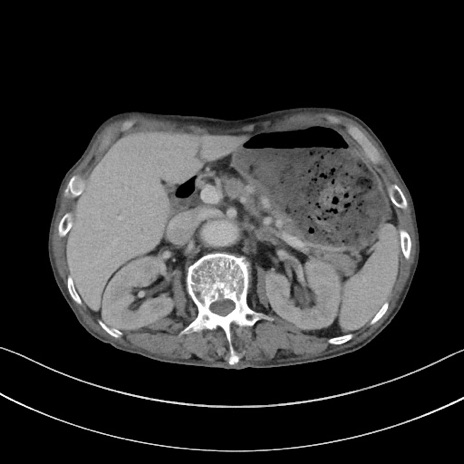

矢状断像

【症例】 70歳代男性

【主訴】右鼠径部腫瘤、疼痛

【現病歴】本日朝より上記主訴あり、受診。

【既往歴】膀胱癌にて膀胱全摘、両側尿管皮膚瘻

【データ】WBC 5600、CRP 0.56